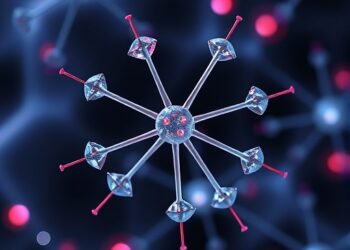

Gold Nanoparticles with miR-199a Combat Liver Cancer

In an exciting advancement that could significantly alter the landscape of cancer therapeutics, researchers have unveiled compelling evidence demonstrating the...